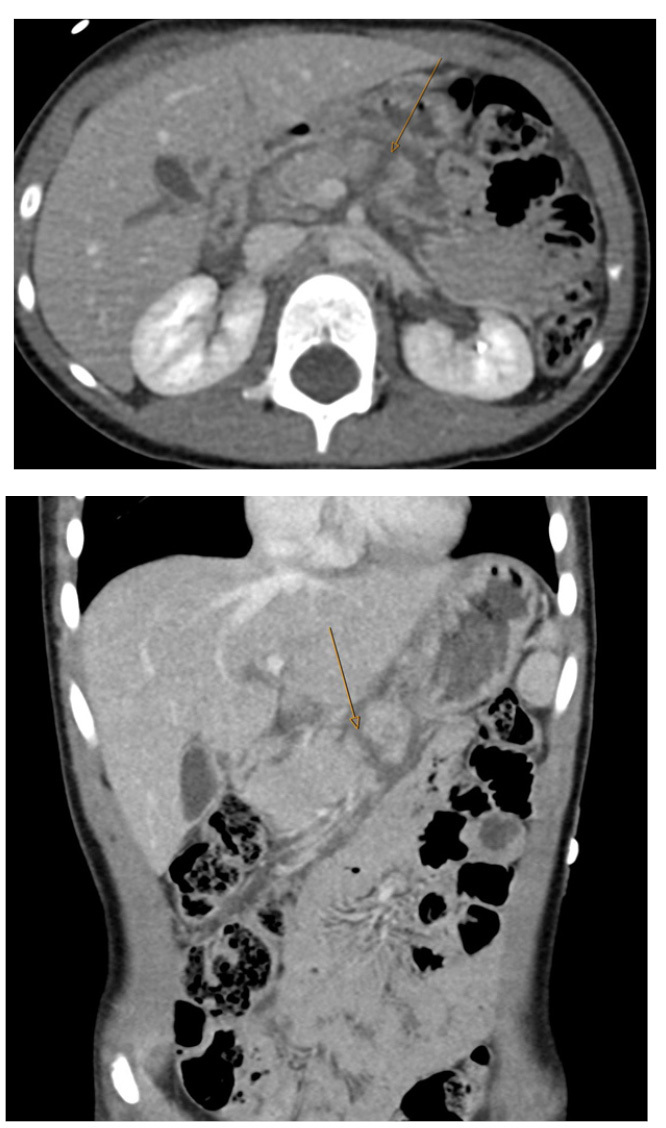

Additional studies have further noted that the PECARN prediction rule, when combined with clinical suspicion, limited the number of CT scans without significant negative consequences.46 Streck et al developed a tool to assess risk and the need for CT scans. The Streck prediction rule includes laboratory results in addition to an abnormal exam and history of abdominal pain. The rule has a negative predictive value of more than 99% in identifying patients without serious intraabdominal injury.47 It has been shown that the implementation of a protocol using such decision tools can significantly decrease the number of abdominal CT scans performed, without increasing the rate of missed injuries.48-50 For an example of a splenic injury, see Figure 4.

Figure 4. Splenic Laceration |

![]() |

Axial and coronal images from computed tomography with intravenous contrast show a splenic laceration with more than 25% of the spleen showing non-enhancement compatible with devascularization, American Association for Surgery of Trauma (AAST) grade 4. Source: Courtesy of Mark Warren, DO, Dayton Children’s Hospital, Department of Radiology |